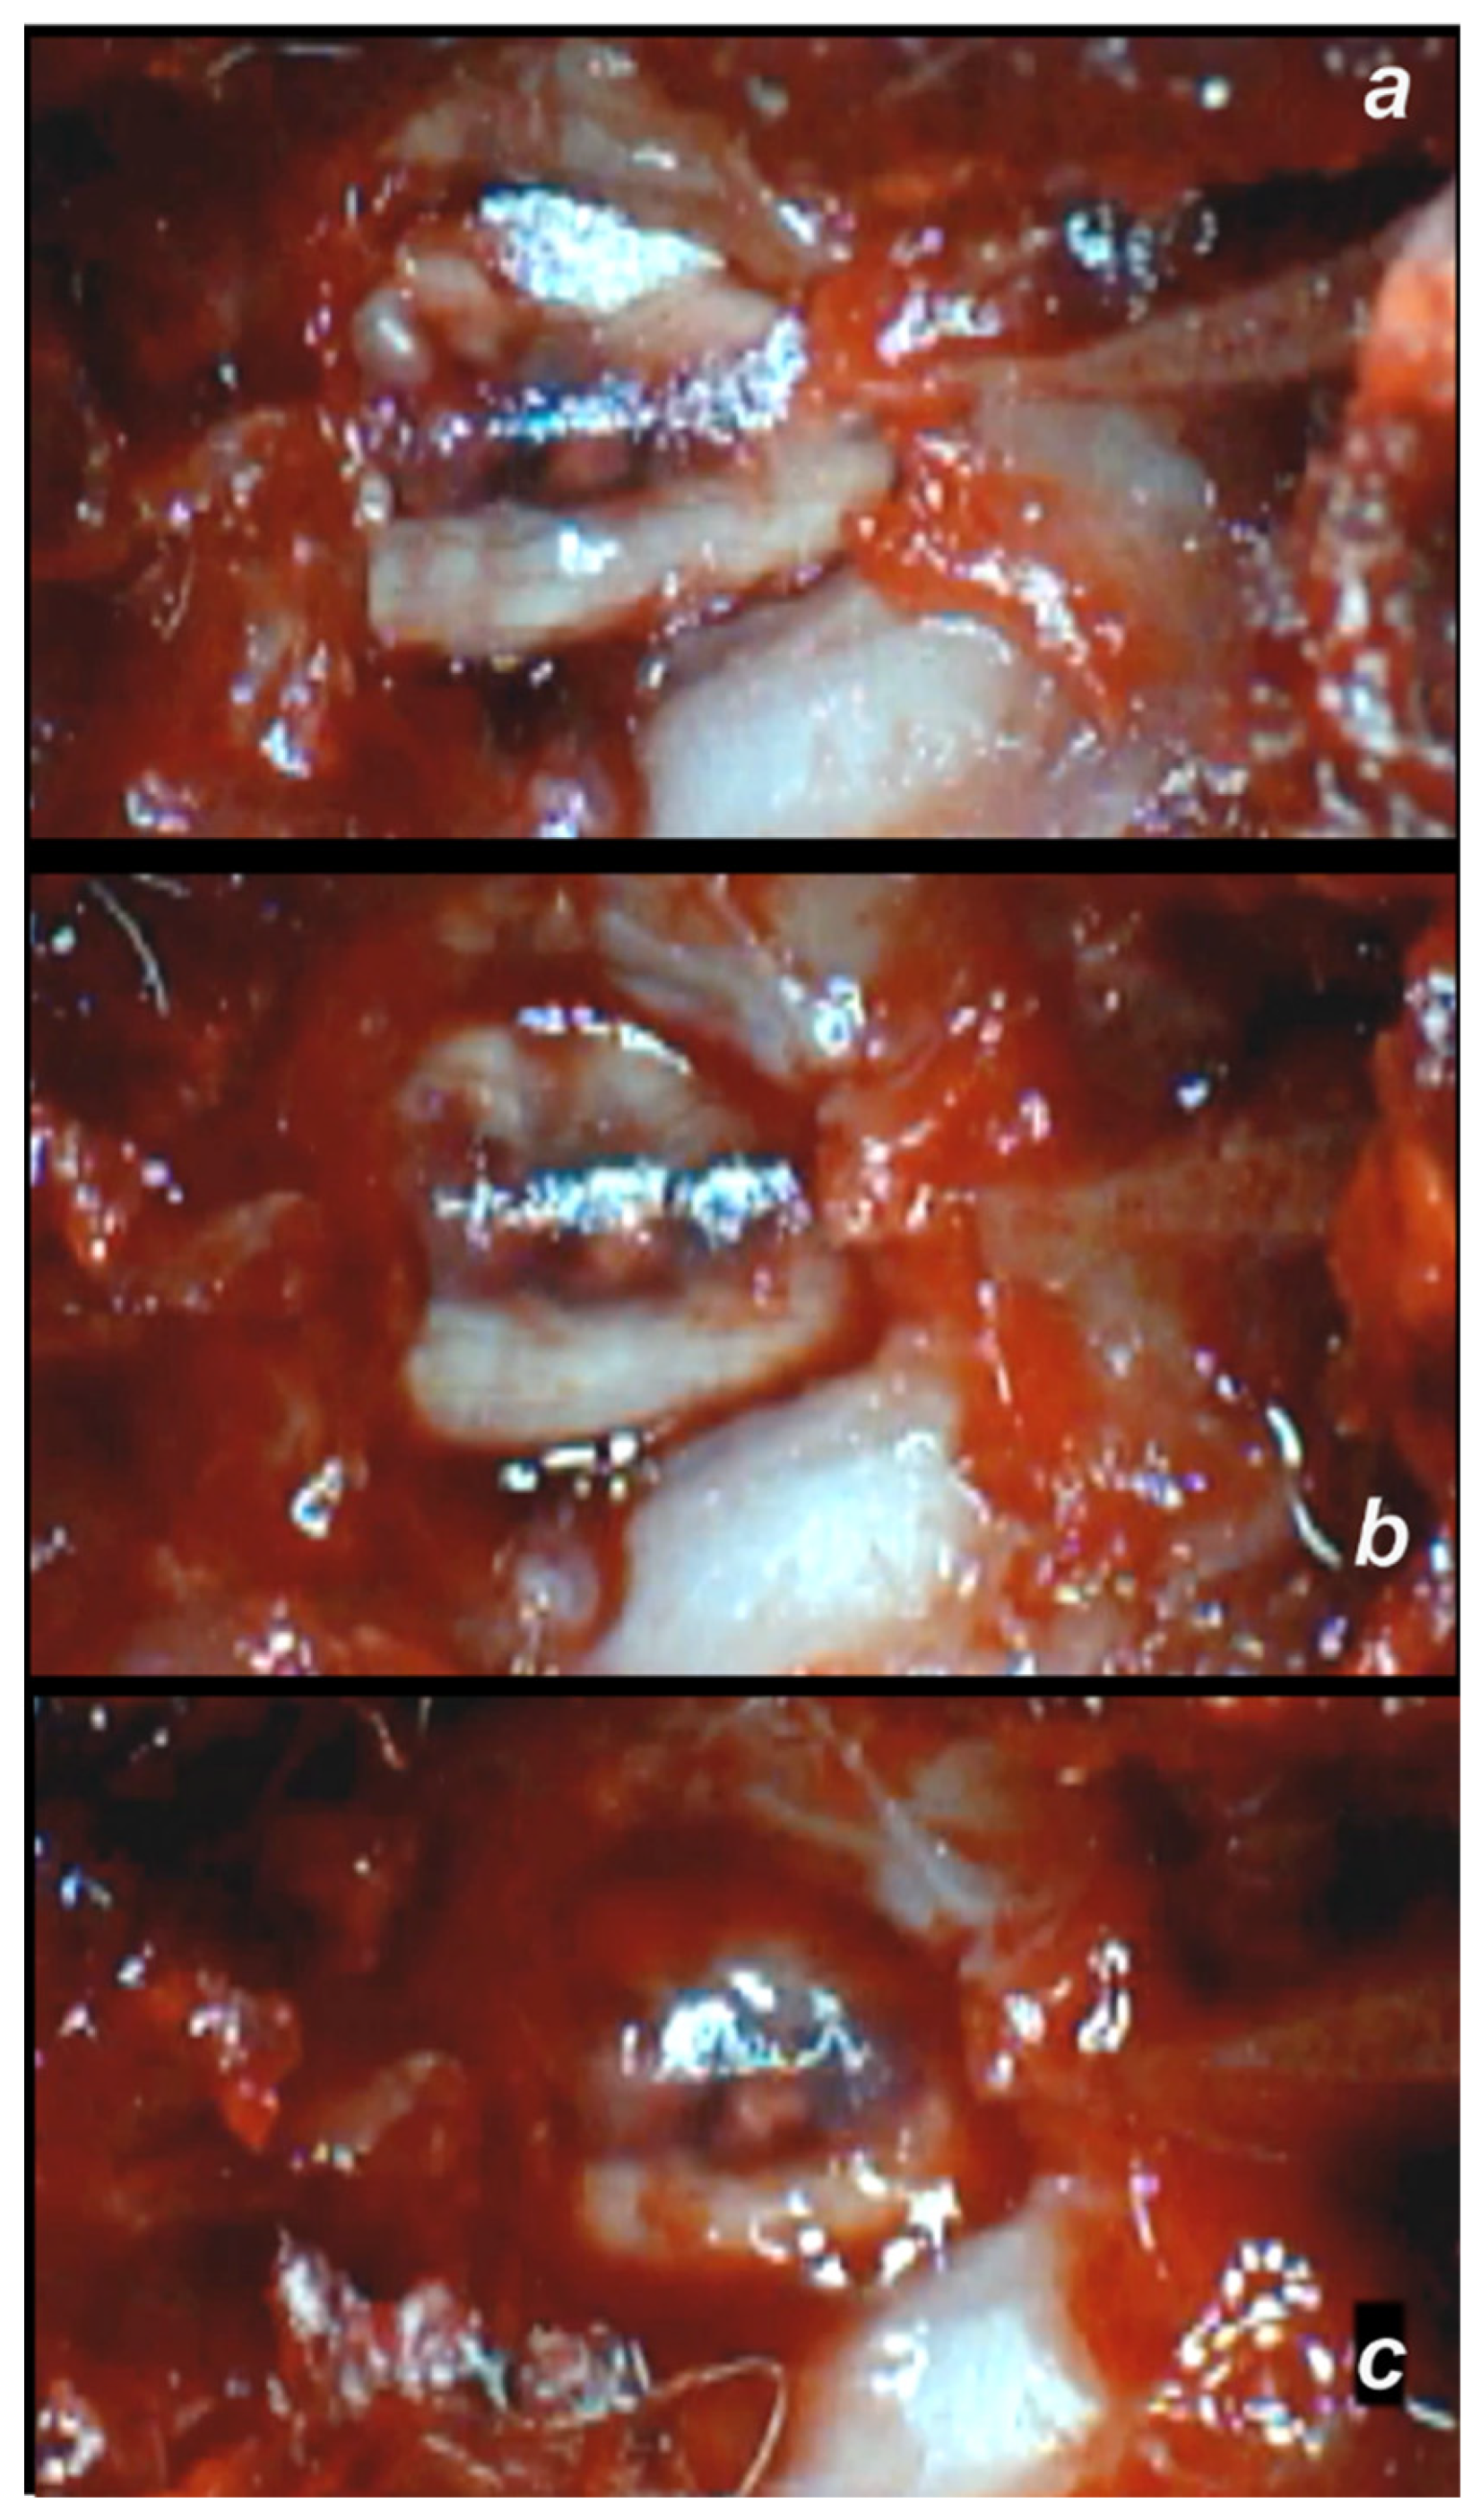

3.2.1. Early Post-Injury Course, Immediate Effect

3.2.2. Delayed Post-Injury Course, Immediate Effect